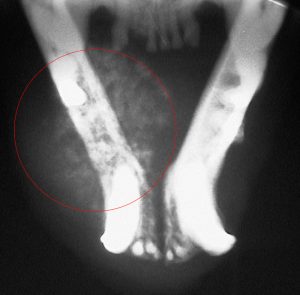

A cancer called Squamous Cell Carcinoma can erode the jaw and cause a spontaneous fracture

The cancerous area is circled in red. Compare it to the other side.